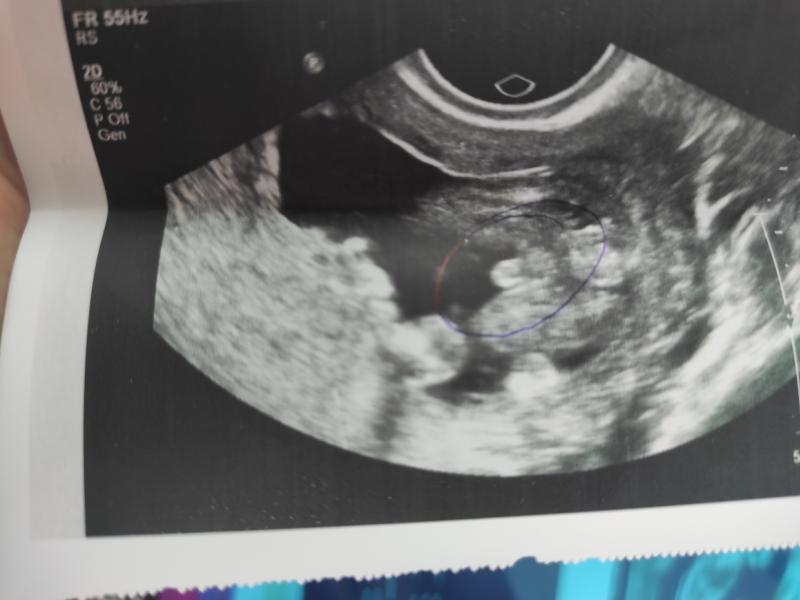

Девочки может кто подскажет, хочу послушать мнение других мамочек. Кто у меня девочка или мальчик.

@oalena489 это мужика попой посадили на сканер, видно ножки и таз и причендалы💙

Просто посмотрела на других форумах, фото там так похоже на яички, но пишут что девочка

Я как-то видела девочку на УЗИ , там на яички похожи, но как-то вытянутые больше, а тут так кругленько и выпукло)) будто вид снизу, а сверху точка, головка полового члена

У меня так сидел ребенок как форель в разрезе. Ничего не было там , но тут в разрезе бубенцы видны. Это похоже мальчик

Возможно мошонка это. Так сложно понять. У меня было фото полностью вид сбоку, там конкретно был отросток, по которому мне сказали типа 100% мальчик. Я почитала различае пола на этом сроке и с мужем сошлись, что 100% девочка. Так и родилась дочка

Вот а к меня фото с низу я так понимаю, с боку не видно вообще ничего... Вот я и не могу понять...

@imbirnaya_ точно, мне все разы говорили на первом УЗИ и без ошибок. Вроде как ещё по углу наклона, если ближе к 45° то мальчишка, меньше торчит и угол - значит это клитор, девочка

Спасибо, просто на УЗИ сказала что не 100% т.к возможно пуповина, лежит не очень удобно)

Да,на таком сроке просто предполагают. У меня сейчас девочка. На всех УЗИ между ног пусто совсем